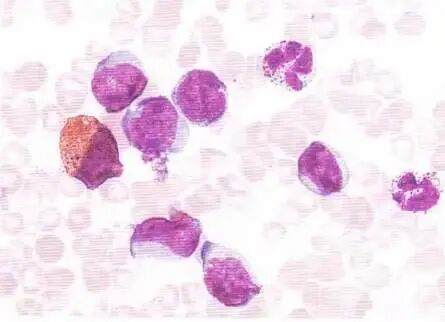

嗜酸性粒细胞性炎症

近90%的鼻息肉组织有较多嗜酸性粒细胞浸润,提示鼻息肉与该细胞增多有密切关系。